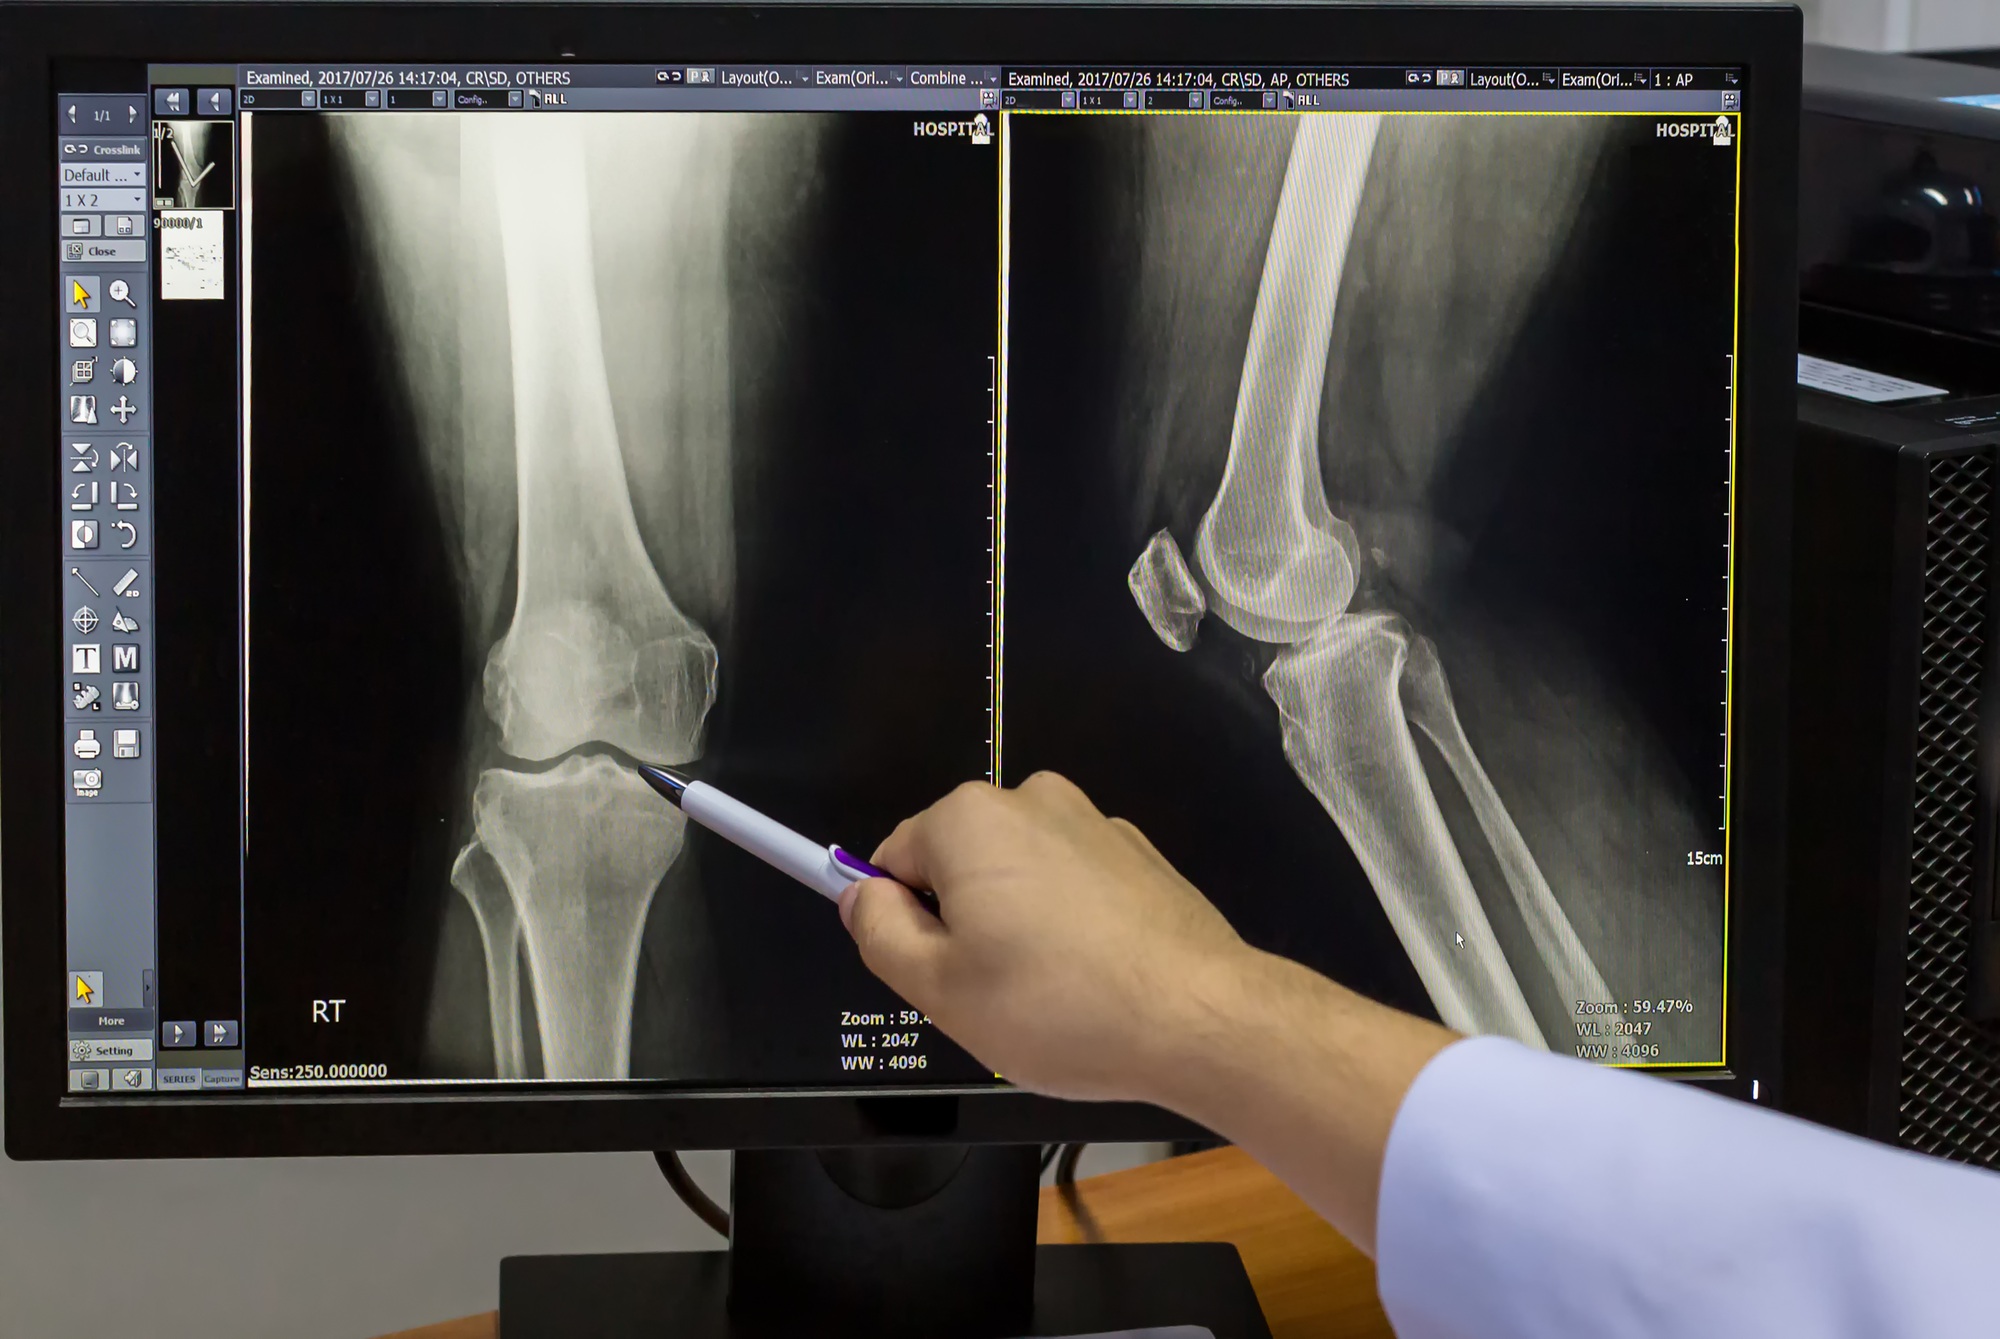

La Clínica de Artrosis del Tolima es tu solución especializada para el manejo de la artrosis y dolores crónicos.

La Clínica de Artrosis del Tolima es tu solución especializada para el manejo de la artrosis y dolores crónicos.

En la Clínica de Artrosis del Tolima, somos expertos en el tratamiento de la artrosis y la osteoporosis. Nuestro enfoque se basa en:

Utilizamos los últimos avances en medicina para garantizarte un tratamiento seguro y efectivo.

Evaluación detallada de tu caso para ofrecerte el mejor plan de tratamiento.